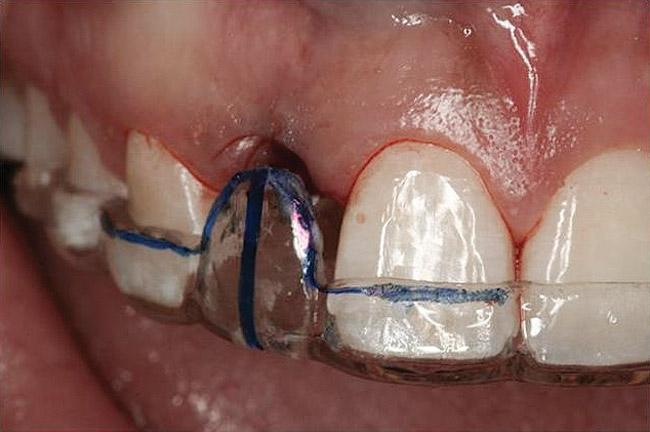

Figure 2  Identification of sufficient inter-radicular space: The radiographic representation of inter-radicular space (Fig 2) reveals abundant space for a single-tooth implant; at the alveolar crest, > 6 mm of interproximal space is available for placement of a 4-mm implant without encroaching on bone and periodontal ligament at the adjacent teeth. The 5-year-follow-up radiograph (Fig 3) reveals the interproximal maintenance of bone at this implant/abutment interface and adjacent teeth, in part due to proper planning and implant placement.

Figure 2

Figure 3  Identification of sufficient inter-radicular space: The radiographic representation of inter-radicular space (Fig 2) reveals abundant space for a single-tooth implant; at the alveolar crest, > 6 mm of interproximal space is available for placement of a 4-mm implant without encroaching on bone and periodontal ligament at the adjacent teeth. The 5-year-follow-up radiograph (Fig 3) reveals the interproximal maintenance of bone at this implant/abutment interface and adjacent teeth, in part due to proper planning and implant placement.

Figure 3